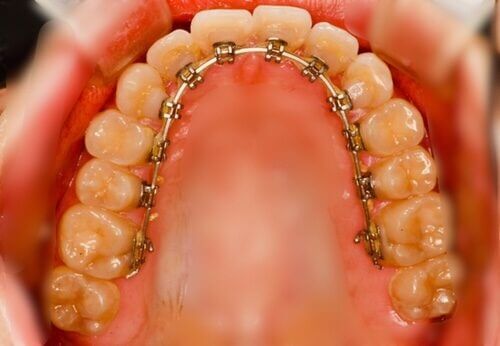

インプラント矯正

(歯科矯正用

アンカースクリュー

を用いた治療)

歯科矯正用アンカースクリューと呼ばれるネジを歯ぐきに埋め込み、これを固定源とすることで矯正治療の効率が高まります。これを「インプラント矯正」といい、インプラント治療と名称は似ていますが仕組みは全く異なります。

歯科矯正用アンカースクリューと呼ばれるネジを歯ぐきに埋め込み、これを固定源とすることで矯正治療の効率が高まります。これを「インプラント矯正」といい、インプラント治療と名称は似ていますが仕組みは全く異なります。

インプラント矯正は従来の約半分程度の期間で歯を理想的な位置へ動かせる治療法です。埋め込むスクリューはわずか数mmなうえに麻酔をしてから埋め込むため、患者さんに大きな負担がかかることはありません。